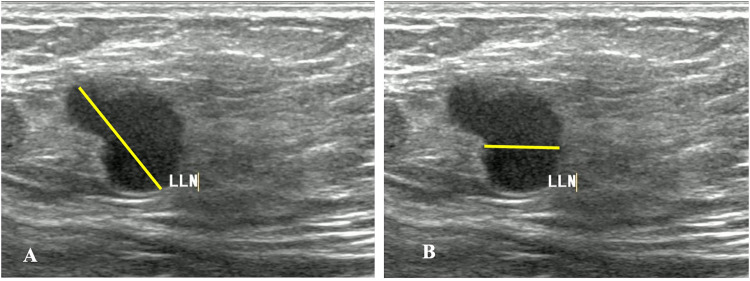

本研究旨在评估一个可解释的机器学习模型在预测术前腋窝淋巴结转移方面的性能,该模型使用原发乳腺癌和来自对比增强乳房x线摄影(CEM)和超声(US)乳房成像报告和数据系统(BI-RADS)的淋巴结特征。方法回顾性研究纳入诊断为原发性乳腺癌的患者。两名经验丰富的放射科医生根据CEM和US图像从病变的最大横截面和腋窝淋巴结中提取BI-RADS特征,创建三个数据集。每个数据集将训练六个基本模型来预测腋窝淋巴结,病理结果作为金标准。前3个模型用于训练5个集成模型。此外,采用SHapley加性解释(SHAP)来解释最优模型。采用受试者工作特征曲线(ROC)和AUC评价模型的性能。结果本研究共纳入292例女性患者,其中99例有腋窝淋巴结转移,193例无腋窝淋巴结转移。超声BI-RADS联合CEM预测腋窝淋巴结转移的效果最好。其中,LightGBM的AUC(0.762)和特异性最高(86.67%),而以RF为元模型的集合模型的AUC(0.754)和特异性最高(83.33%)。SHAP确定的最重要的变量是CEM重组图像中淋巴结的长直径,以及低能图像中淋巴结的完整形态。结论基于CEM和US BI-RADS特征的机器学习模型可以准确预测乳腺癌患者术前腋窝淋巴结转移,为乳腺癌患者的临床决策提供有价值的工具。

IntroductionThe study aims to evaluate the performance of an interpretable machine learning model in predicting preoperative axillary lymph node metastasis using primary breast cancer and lymph node features derived from contrast-enhanced mammography (CEM) and ultrasound (US) breast imaging reporting and data systems (BI-RADS).MethodsThis retrospective study included patients diagnosed with primary breast cancer. Two experienced radiologists extracted the BI-RADS features from the largest cross-section of the lesions and axillary lymph nodes based on CEM and US images, creating three datasets. Each dataset will train six base models to predict axillary lymph nodes, with pathological results serving as the gold standard. The top three models were used to train the five ensemble models. Additionally, SHapley Additive exPlanations (SHAP) was used to interpret the optimal model. The receiver-operating characteristic curve (ROC) and AUC were used to evaluate model performance.ResultsThis study involved 292 female patients, of whom 99 had axillary lymph node metastasis and 193 did not. The combination of CEM and ultrasound BI-RADS demonstrated the best performance in predicting axillary lymph node metastasis. Among these, the LightGBM achieved the highest AUC (0.762) and specificity (86.67%, while the ensemble model using RF as the meta-model had an AUC (0.754) and specificity (83.33%. The most important variables identified by SHAP were the long diameters of the lymph nodes in the CEM recombined image, along with their complete morphology in the low-energy image.ConclusionThe machine learning model using CEM and US BI-RADS features accurately predicted axillary lymph node metastasis before surgery, thereby serving as a valuable tool for clinical decision-making in patients with breast cancer.